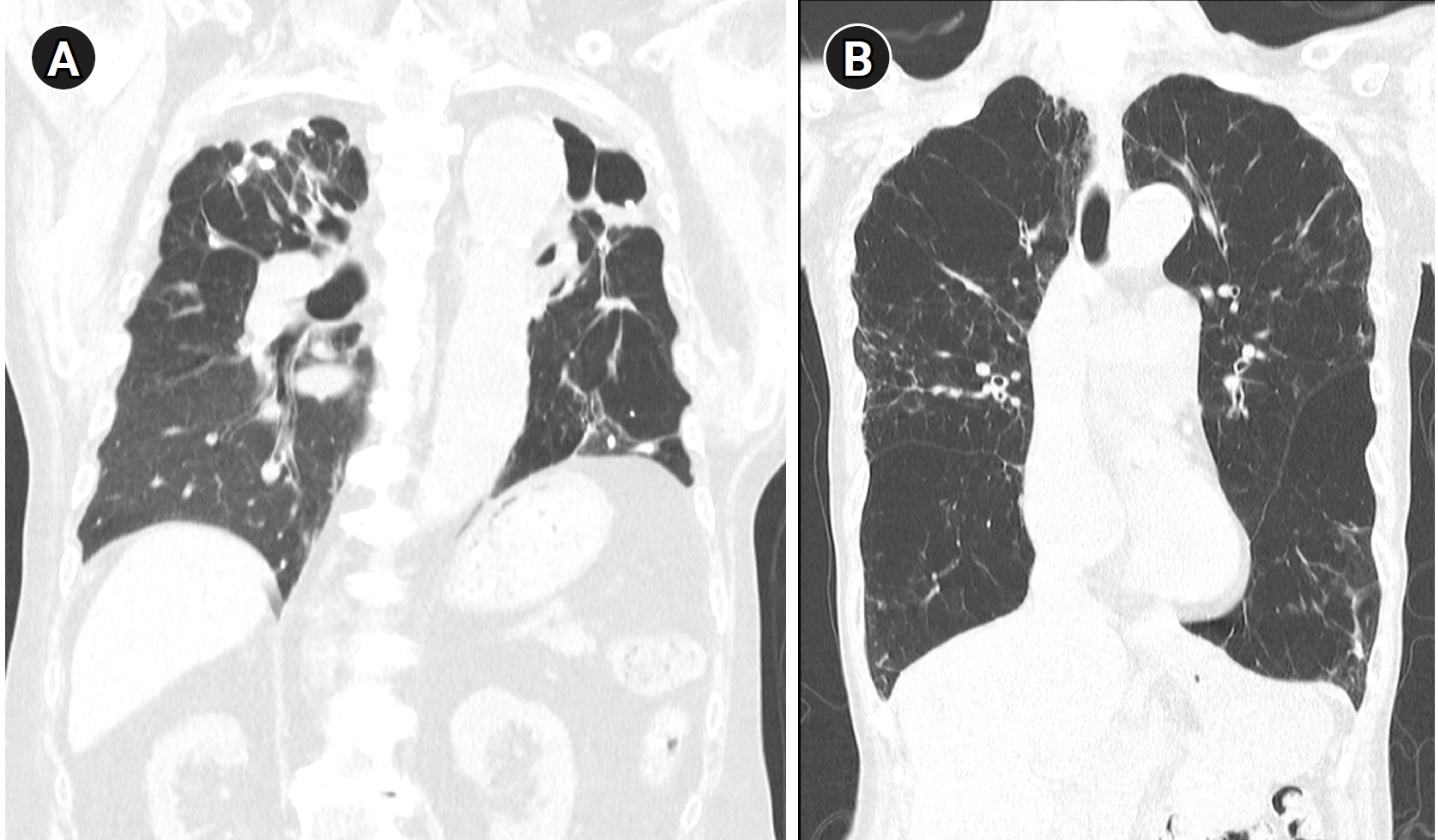

특히 본 논문은 TB-COPD의 발병 기전에 있어 과도한 면역 반응, 기질분해효소(MMP)의 과발현, 호중구 매개 염증이 핵심적인 역할을 한다는 점을 강조합니다. 결핵 치료 후에도 지속되는 폐 손상이 COPD의 발병과 악화에 어떻게 영향을 미치는지에 대한 병태생리적 설명은 이 질환에 대한 이해를 심화시킵니다. 또한, TB-COPD는 기존의 흡연 관련 COPD와는 영상학적·기능적으로 구별되는 특징을 가지며, 치료 전략에 있어서도 장기작용 기관지확장제(LABA, LAMA)와 선택적 흡입 스테로이드의 신중한 활용이 필요함을 시사합니다. Indacaterol과 Tiotropium의 임상적 유효성에 대한 근거도 함께 제시되어, 향후 치료 접근에 실질적인 도움을 줄 수 있습니다.